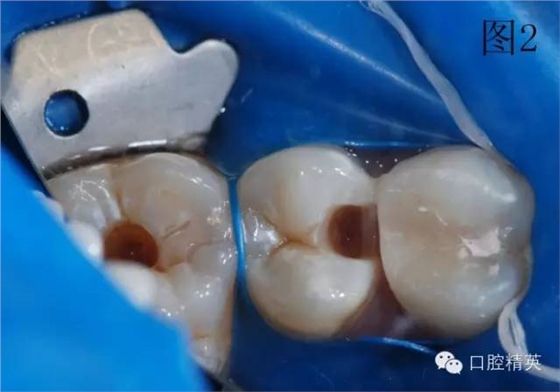

圖2、3為左上第一前磨牙充填結(jié)束,上橡皮障,充填另外兩顆牙。使用橡皮障,可以嚴密隔濕,防止樹脂受到污染,增加樹脂與牙齒之間的粘結(jié)力,延長充填物的使用壽命。